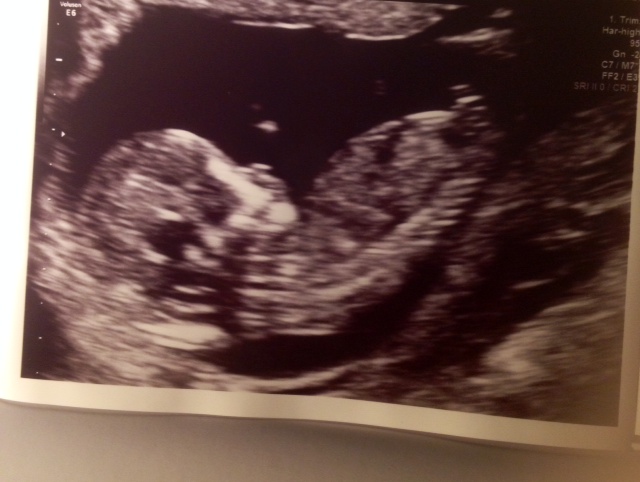

is it boy or girl?

the thing sticking up is part of the leg, so I find it very hard to see. We are hoping on a girl but will of course love the child no matter what gender can anyone see which gender it is based on this photo and how?

Sorry I can't see the nub.

Sorry, I'm having trouble making out a clear nub in this pic. Congratulations though and fingers crossed for your girl x

That's too close to spine for nub I am sorry to say I think boy as I see something sticking up if I have permission I could upload your photo to edit and show you then delete your photo x

It does look very similar to my sons with the nobbly bit at the top turns out my update stopped me been able to draw on photos anyway x

No nub visible. Sorry! But I would guess girl based on skull shape but that's not very reliable. Congrats!